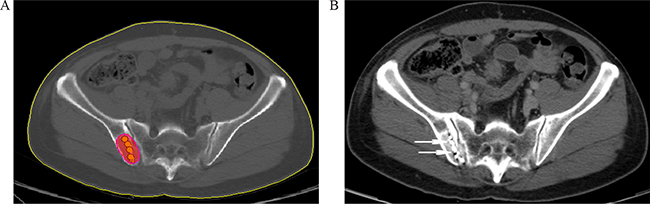

On the day of the procedure, the patient was pasitioned on the CT gantry and treatment site was localized. 5mm axial slices were obtained to delineate the upper and lower borders of the tumor. After local infiltration anesthesia with 5-15 mL of 1% lidocaine (Liduokayin; Yimin, Yichang, China), an 18 G spinal needle (Yunke Pharmaceutical Limited Liability Company, Chengdu, China) reached the farthest tumor edge, but was kept at approximately or less than 5 mm of the border (Figure 2). A turntable or clip implant gun (Yunke Pharmaceutical Limited Liability Company, Chengdu, China) was then attached to the applicator for implantation. From deep to shallow, the particles were released while retracting the needle and keeping adjacent particles at a distance of 5–15 mm. To avoid introprocedural complications, all of the spinal needles were retained until the implantation was completed and then removed simultaneously. A completion CT scan was performed to assess for postoperative complications such as bleeding. The last scan image was also reviewed to verify the position and intensity of 125I seeds according to TPS (Figure 3A, 3B). If a lesion demonstrated insufficient radioactivity, the procedure was repeated for additional 125I implantation.

Figure 2: CT -guided percutaneous 125I seed implantation was performed according to preoperative TPS plan, a 18 G spinal needle reached the tumor (arrowhead). From deep to shallow, the particles were released.

Figure 3: A. Verification of post-125I brachytherapy. the PTV edge was covered by isodose curve. B. Two weeks after brachytherapy, the tumor kept stable, with well distributed radioactive seeds remaining (arrowhead).